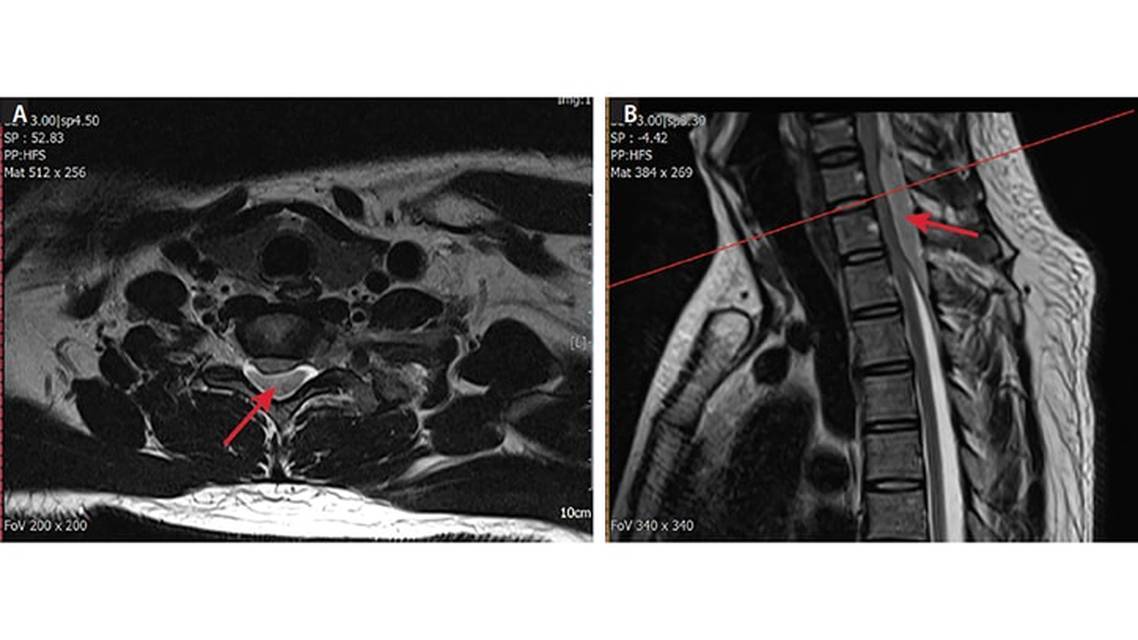

Mr. I was sent for an emergent cervicothoracic MRI and findings showed a large dorsal epidural hematoma with severe spinal cord compression from C5 to T2 (Figure 1). His preoperative laboratory values including coagulation studies were unremarkable. Immediately after MRI, Mr. I was noted to have flaccid paralysis of his lower extremities, no rectal tone, and progressive upper extremity weakness with a sensory level at C5 (ASIA-A impairment, Table).